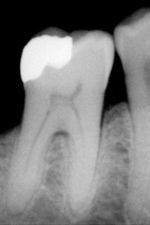

Most dental restorations involve the removal of enamel. Frequently, the purpose of removal is to gain access to the underlying decay in the dentin or inflammation in the pulp. This is typically the case in amalgam restorations and endodontic treatment.

Nonetheless, enamel can sometimes be removed before there is any decay present. The most popular example is the dental sealant. The process of placing dental sealants in the past involved removing enamel in the deep fissures and grooves of a tooth and replacing it with a restorative material. Presently, it is more common to only remove decayed enamel if present. In spite of this, there are still cases where deep fissures and grooves in enamel are removed in order to prevent decay, and a sealant may or may not be placed depending on the situation. Sealants are unique in that they are preventative restorations for protection from future decay and have shown to reduce the risk of decay by 55% over 7 years.

Aesthetics is another reason for the removal of enamel. Removing enamel is necessary when placing crowns and veneers to enhance the appearance of teeth. In both of these instances, it is important to keep in mind the orientation of enamel rods because it is possible to leave enamel unsupported by underlying dentin, leaving that portion of the prepared teeth more vulnerable to fracture.